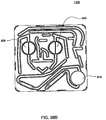

- Fig. 1 is a schematic representation of a hemodialysis system.

- the system 5 includes two flow paths, a blood flow path 10 and a dialysate flow path 20.

- Blood is drawn from a patient.

- a blood flow pump 13 causes the blood to flow around blood flow path 10, drawing the blood from the patient, causing the blood to pass through the dialyzer 14, and returning the blood to the patient.

- the blood may pass through other components, such as a filter and/or an air trap 19, before returning to the patient.

- anticoagulant may be supplied from an anticoagulant supply 11 via an anticoagulant valve 12.

- a dialysate pump 15 draws dialysate from a dialysate supply 16 and causes the dialysate to pass through the dialyzer 14, after which the dialysate can pass through a waste valve 18 and/or return to the dialysate feed via dialysate pump 15.

- a dialysate valve 17 controls the flow of dialysate from the dialysate supply 16.

- the dialyzer is a type of filter having a semi-permeable membrane, and is constructed such that the blood from the blood flow circuit flows through tiny tubes and the dialysate solution circulates around the outside of the tubes. Therapy is achieved by the passing of waste molecules (e.g., urea, creatinine, etc.) and water from the blood through the walls of the tubes and into the dialysate solution. At the end of treatment, the dialysate solution is discarded.